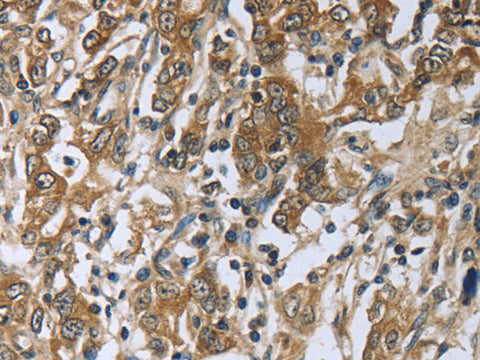

PRL Polyclonal Antibody Store at -20°C

Reactivity Human

Applications IHC

IHC 1:50-1:200

This gene encodes the anterior pituitary hormone prolactin. This secreted hormone is a growth regulator for many tissues, including cells of the immune system. It may also play a role in cell survival by suppressing apoptosis, and it is essential for lactation. Alternative splicing results in multiple transcript variants that encode the same protein.